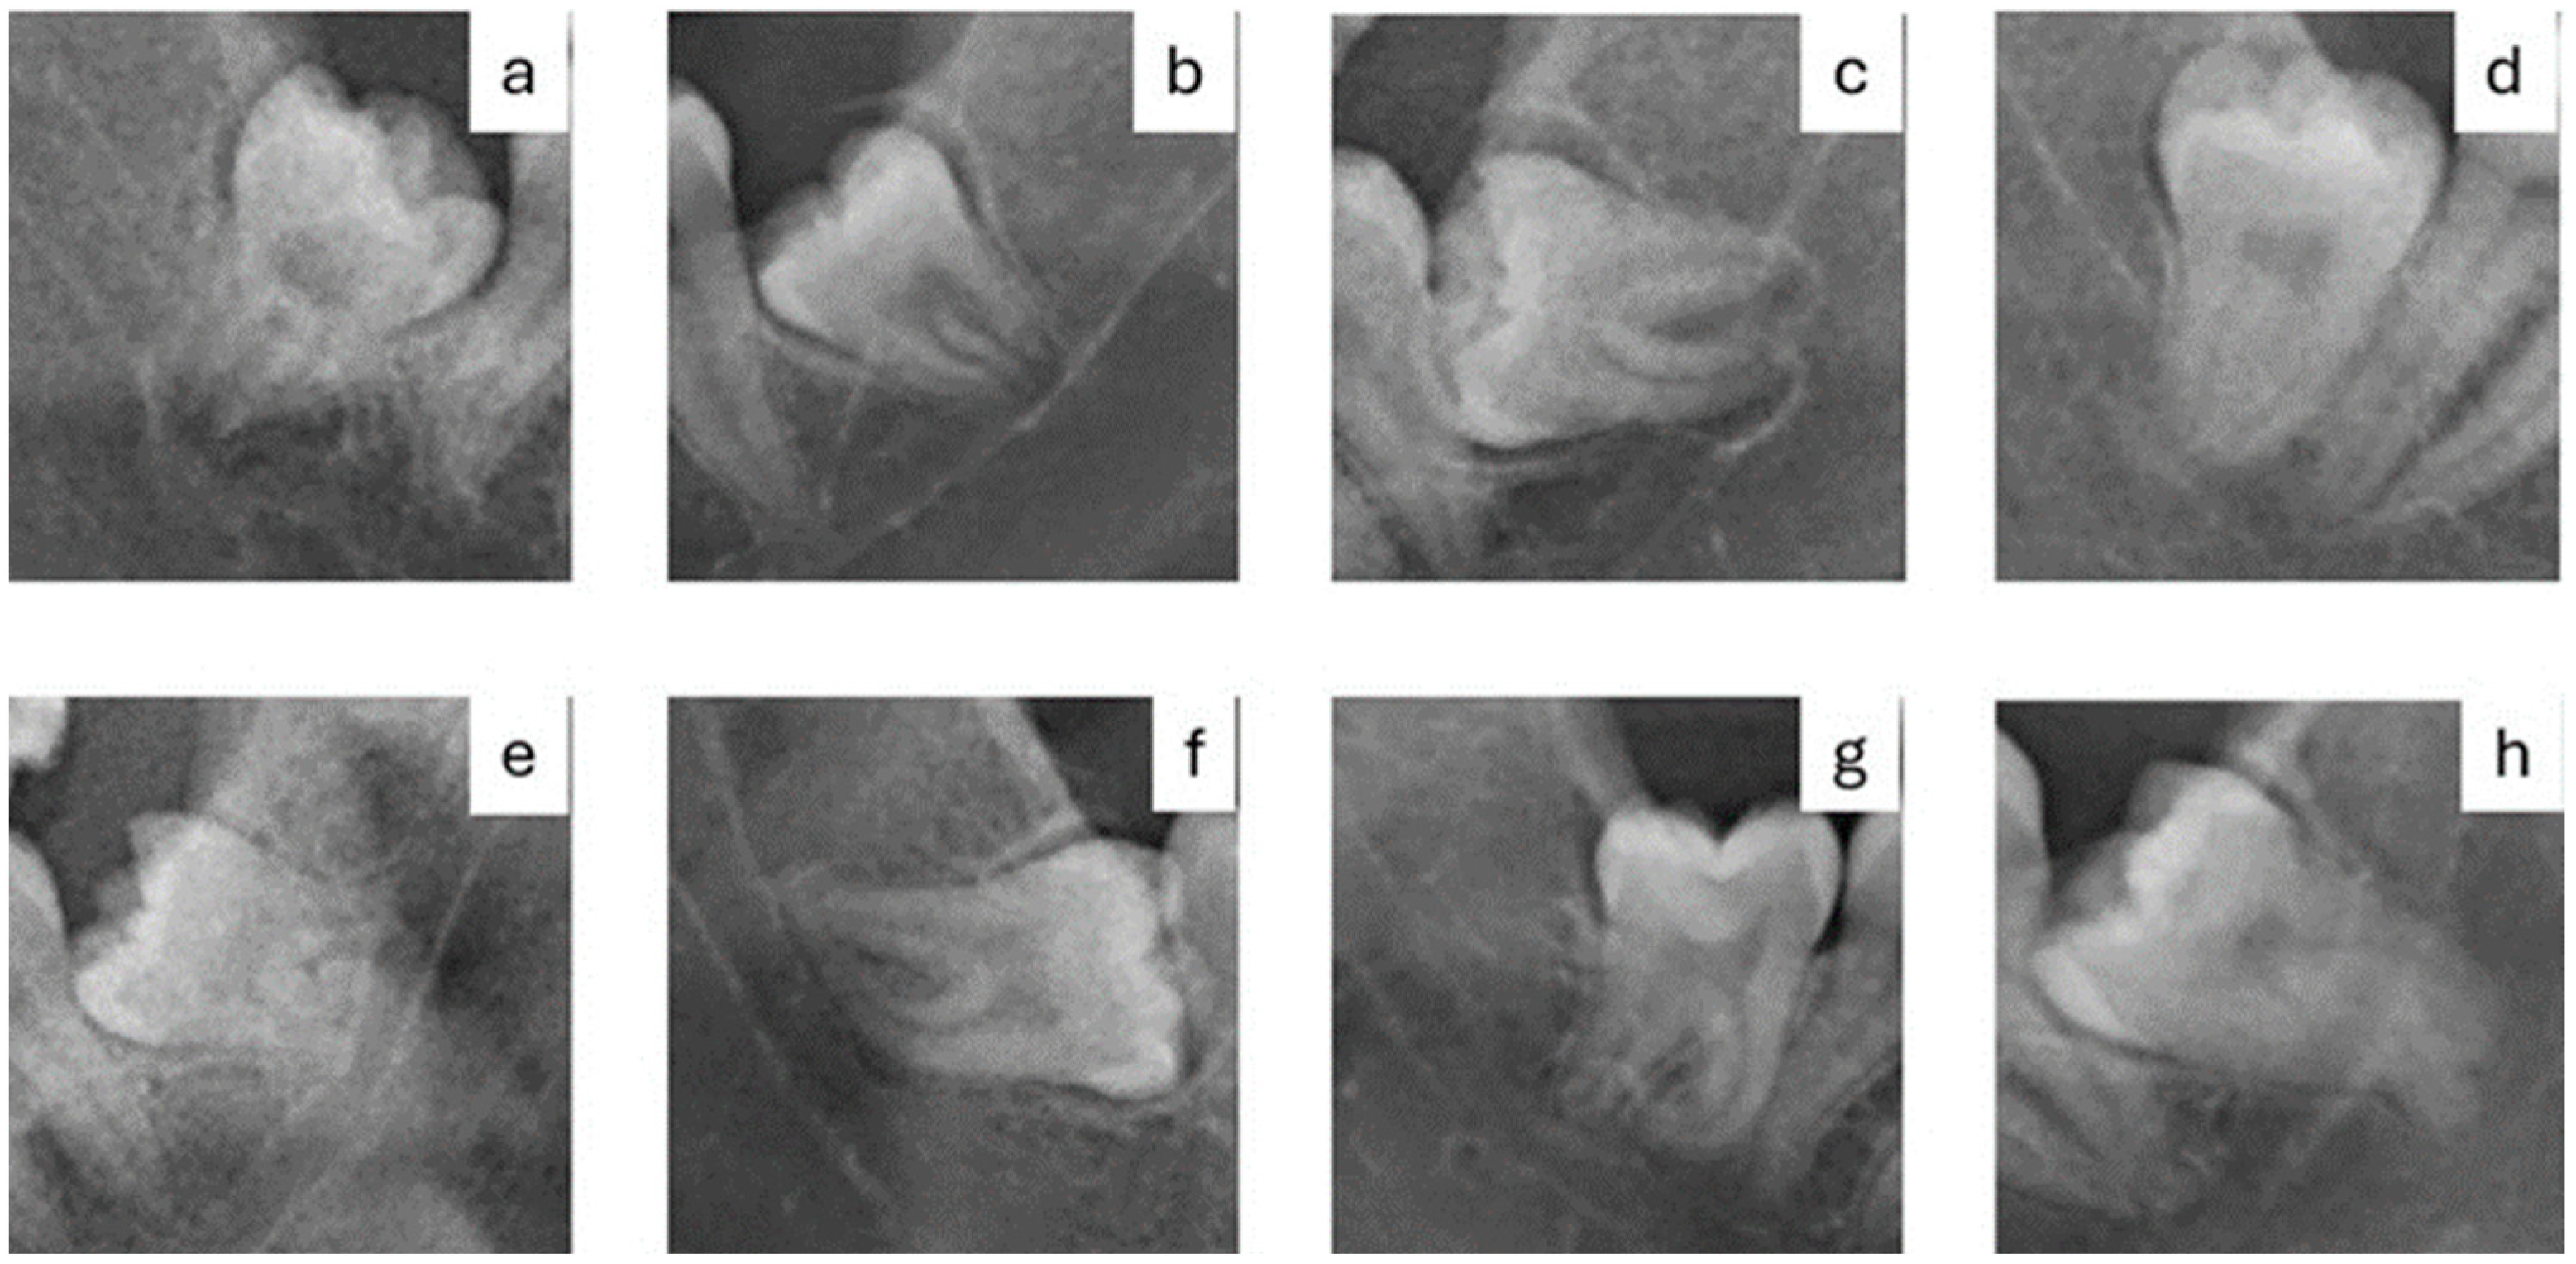

- a)

- Radiolucency at the root

- b)

- Narrowing of the root

- c)

- Radiolucency and bifurcation at the root apex

- d)

- Discontinuity of the mandibular canal cortex

- e)

- Narrowing of the mandibular canal

- f)

- Deviation of the root

- g)

- Deviation of the mandibular canal

- h)

- Superimposition of the root and the mandibular canal (overlapping)